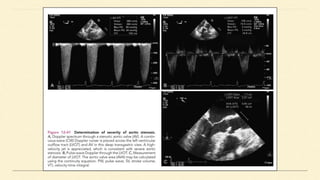

TEE EVALUATION

The primary haemodynamic parameters recommended for TEE evaluation of AS

severity are:

● AS jet velocity

● Mean transaortic gradient

● Valve area by continuity equation

AVA - CONTINUITY EQUATION

Aortic valve area is calculated based on the continuity-equation concept that the

stroke volume (SV) ejected through the LV outflow tract (LVOT) all passes through

the stenotic orifice (AVA) and thus SV is equal at both sites:

Calculation of continuity-equation valve area requires three measurements:

● AS jet velocity by CWD

● LVOT diameter

● LVOT velocity by PWD